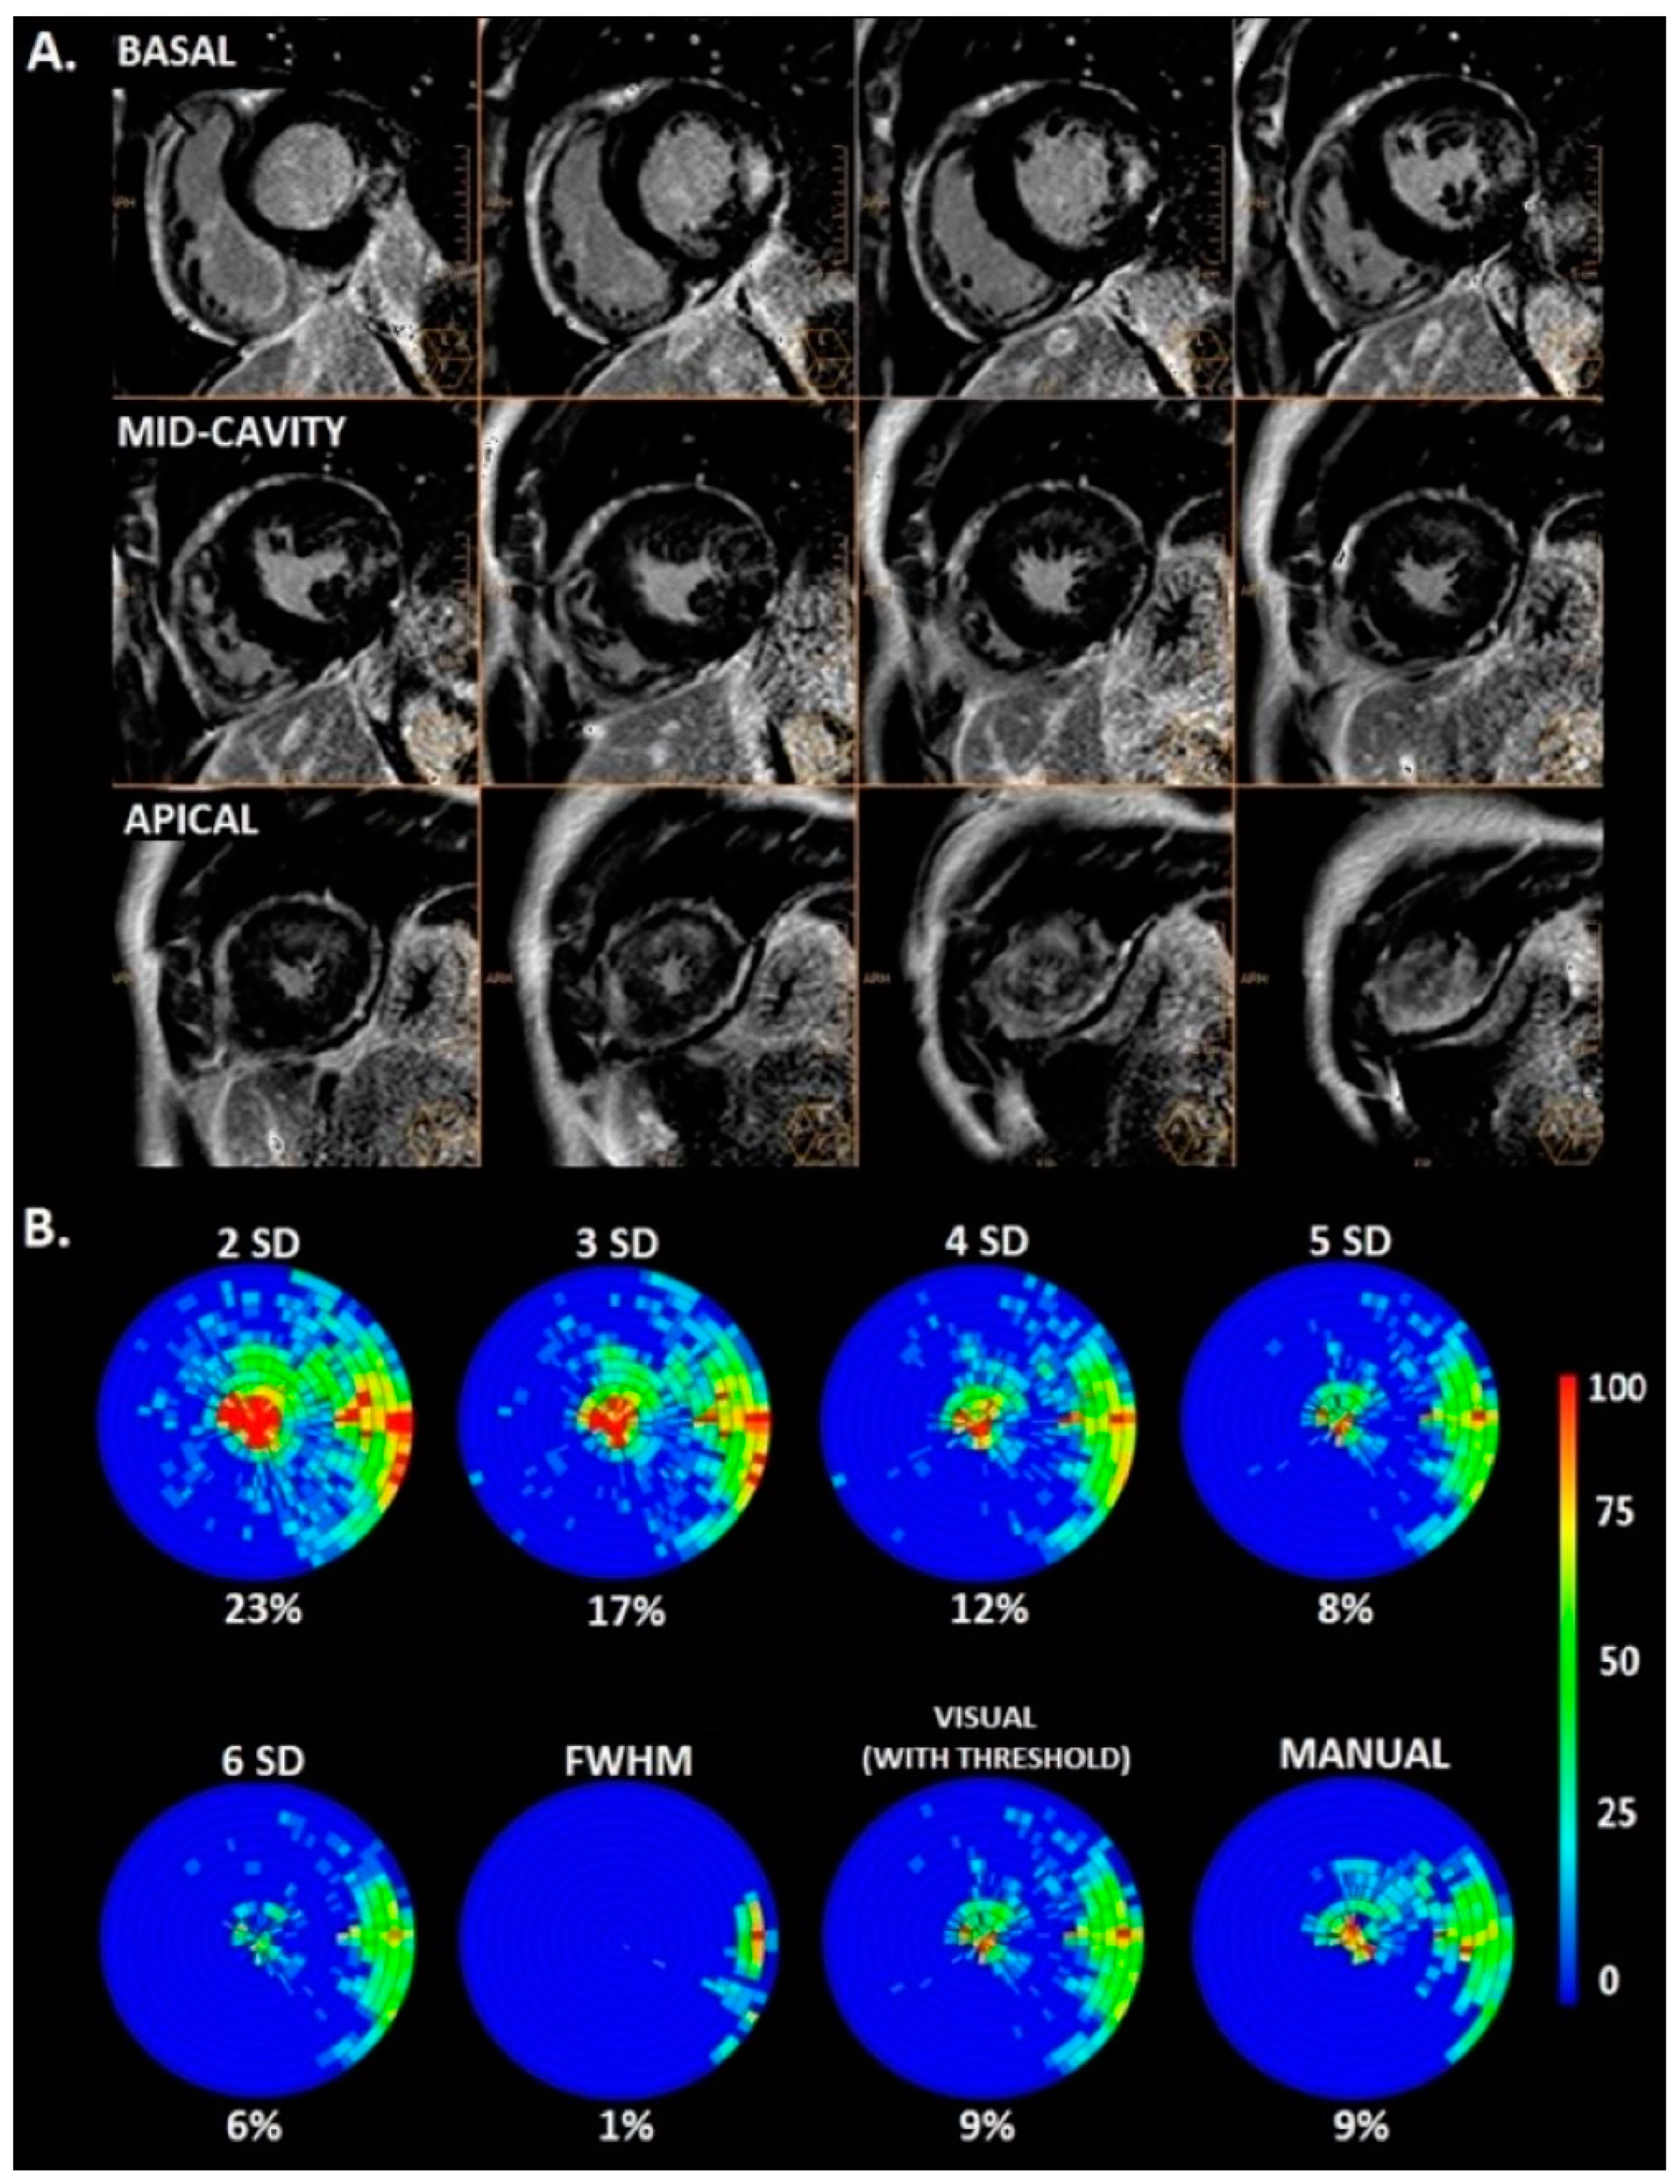

3.2. Amount of LGE

3.3. Intraobserver and Interobserver Reliability and Reproducibility